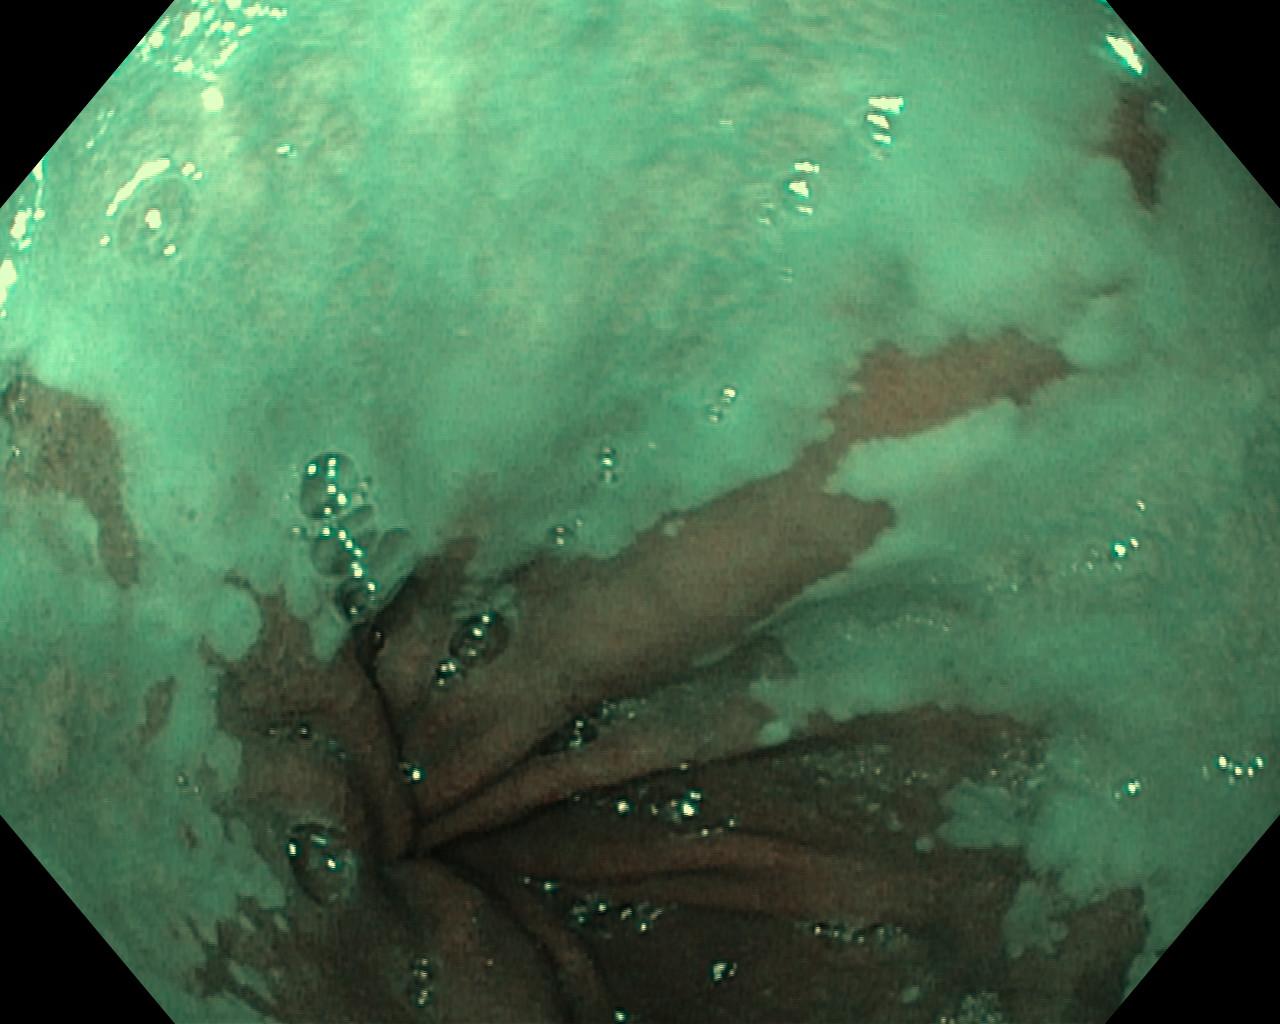

Przełyk Barretta